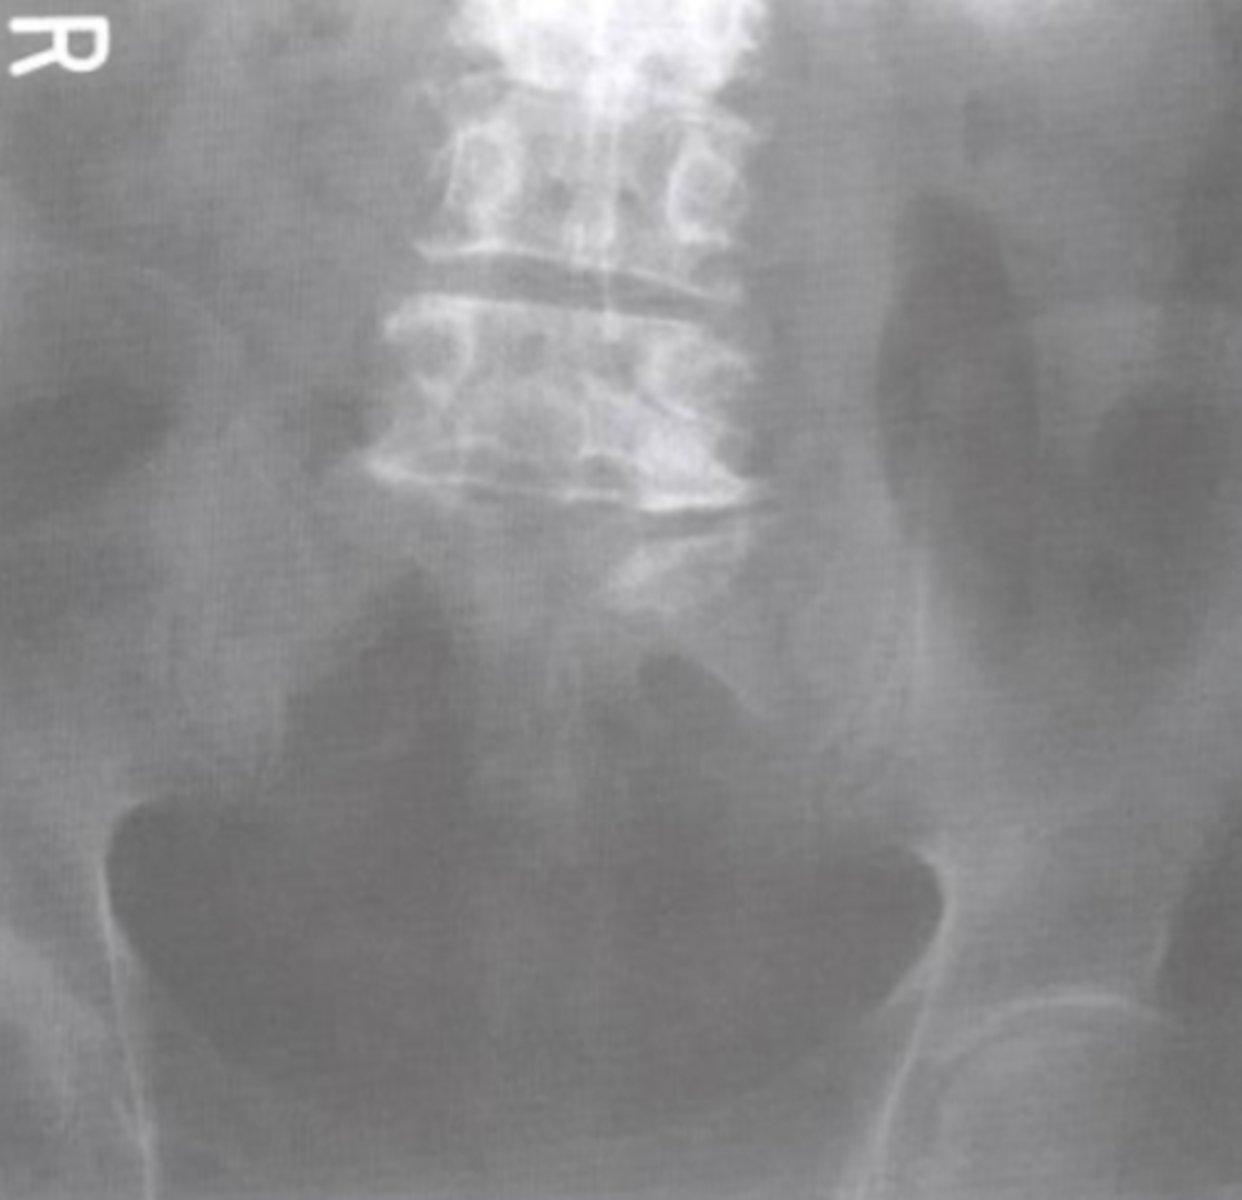

AP Axial SIJ

What view is this?